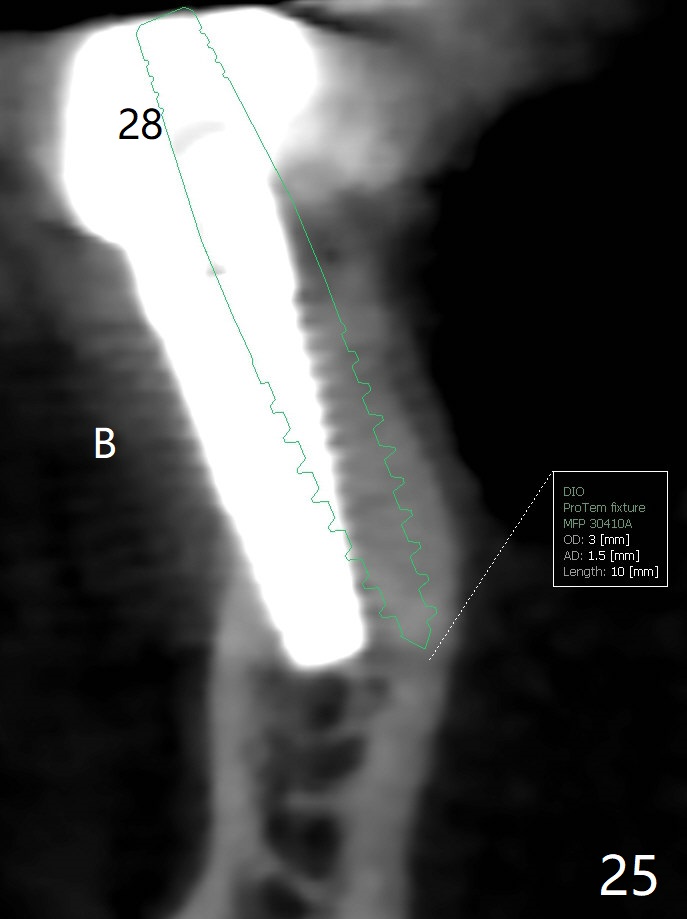

The edentulous ridge at #30 is narrow (Fig.1). After ridge reduction, osteotomy is initiated with 1.2 mm drill for 10 mm; the mesial osteotomy is to be changed (Fig.2 red line). Using a 1.2 mm drill placed in the distal osteotomy (Fig.3 D), the mesial osteotomy changes in trajectory with subsequent placement of a 2.5x10(4) mm 1-piece implant. Since the mesial implant is high in occlusion, the cuff of the distal implant is changed to be 2 mm (Fig.4 (shorter black line)). Panoramic X-ray is taken to show no violation of the Inferior Alveolar Canal (Fig.5 red dashed line). These two 1-piece implants are slightly lingually placed (Fig.6). The crestal bone around the implants resorbs without thread exposure 5 months postop (Fig.7). Impression is taken for a splinted crown (Fig.8-12). There is no metal show around the 2.5 mm 1-piece implants 6 months postop (advantage) vs. that at #28 and 29 (Fig.13). Bitewing is taken post cementation to determine whether residual cement is present (Fig.14). There is periodic swelling and pain in the lower right quadrant 2 years post cementation (Fig.15). In fact periimplantitis appears to have developed at #28 (Fig.16) with loss of the buccal bone (Fig.17,18). The buccal bone loss is less at #29 (Fig.19) and #20 (Fig.23) and no at #30 mesial and distal implants (Fig.20,21). A much smaller implant will be placed lingually at #28 immediate (Fig.24,25).